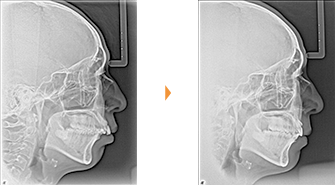

| 主訴 | 上の前歯が出ている、下の前歯がでこぼこ |

| 年齢・性別 | 20歳 / 女性 |

| 治療方針 | 上下顎前歯部に叢生があり、オーバージェットが大きい上顎前突。下顎の時計回りの回転が著しく下顎の後退感が強い。プロファイルの改善は困難が予想される。 |

| 抜歯部位 | 小臼歯4本抜歯 |

| 使用装置 | マルチブラケット装置、トランスパラタルアーチ、歯科矯正用アンカースクリュー |

| 治療期間 | 34か月 |

| リテーナー | 上顎インビジブル、下顎スプリングリテーナー |

| 費用 | 885,000円(税別) |